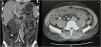

During hospitalization, lupus enteritis was diagnosed on day 4 due to the presence of abdominal pain, diarrhea and a contrast-enhanced CT scan with a target sign in the distal ileum (Fig. 1). In addition, due to an episode of thunderclap headache (day 7) a brain angioresonance was performed, which detected thrombosis at the confluence of the transverse, left sigmoid and superior sagittal venous sinuses (Fig. 2; Table 1). Due to these findings, immunoglobulin infusion and anticoagulation were started.